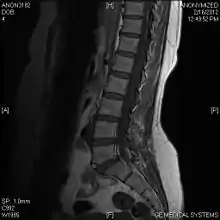

T1 W Sagittal

Limbus Vertebra L5